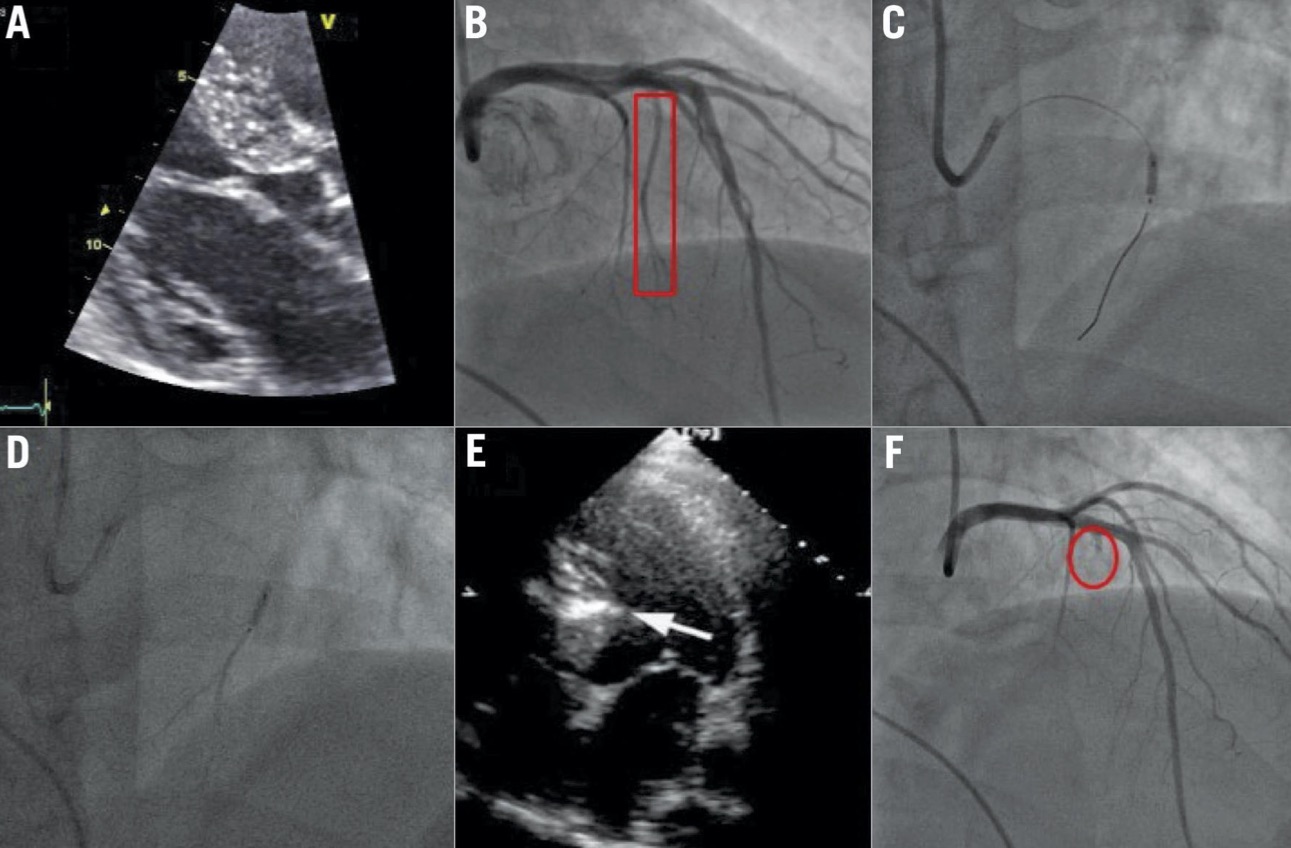

- Mediante coronarografia si individua il ramo dell’arteria coronarica sinistra che irrora la zona del setto interventricolare che ostruisce l’efflusso del ventricolo sinistro (ramo settale).

- Mediante Ecocardiografia con mezzo di contrasto si conferma che la zona dove giungerà l’alcool iniettato nel ramo settale corrisponde alla zona del setto interventricolare ipertrofico responsabile dell’ostruzione.

- Si inietta allora una piccola quantità di alcool puro (1-2 cc) e in tal modo si blocca la funzione della porzione di setto interventricolare dove si localizza l’alcool. Così si provoca un infarto, limitato alla zona ipertrofica. L’ostruzione si riduce o scompare immediatamente

Immagini – Alcoolizzazione settale percutanea